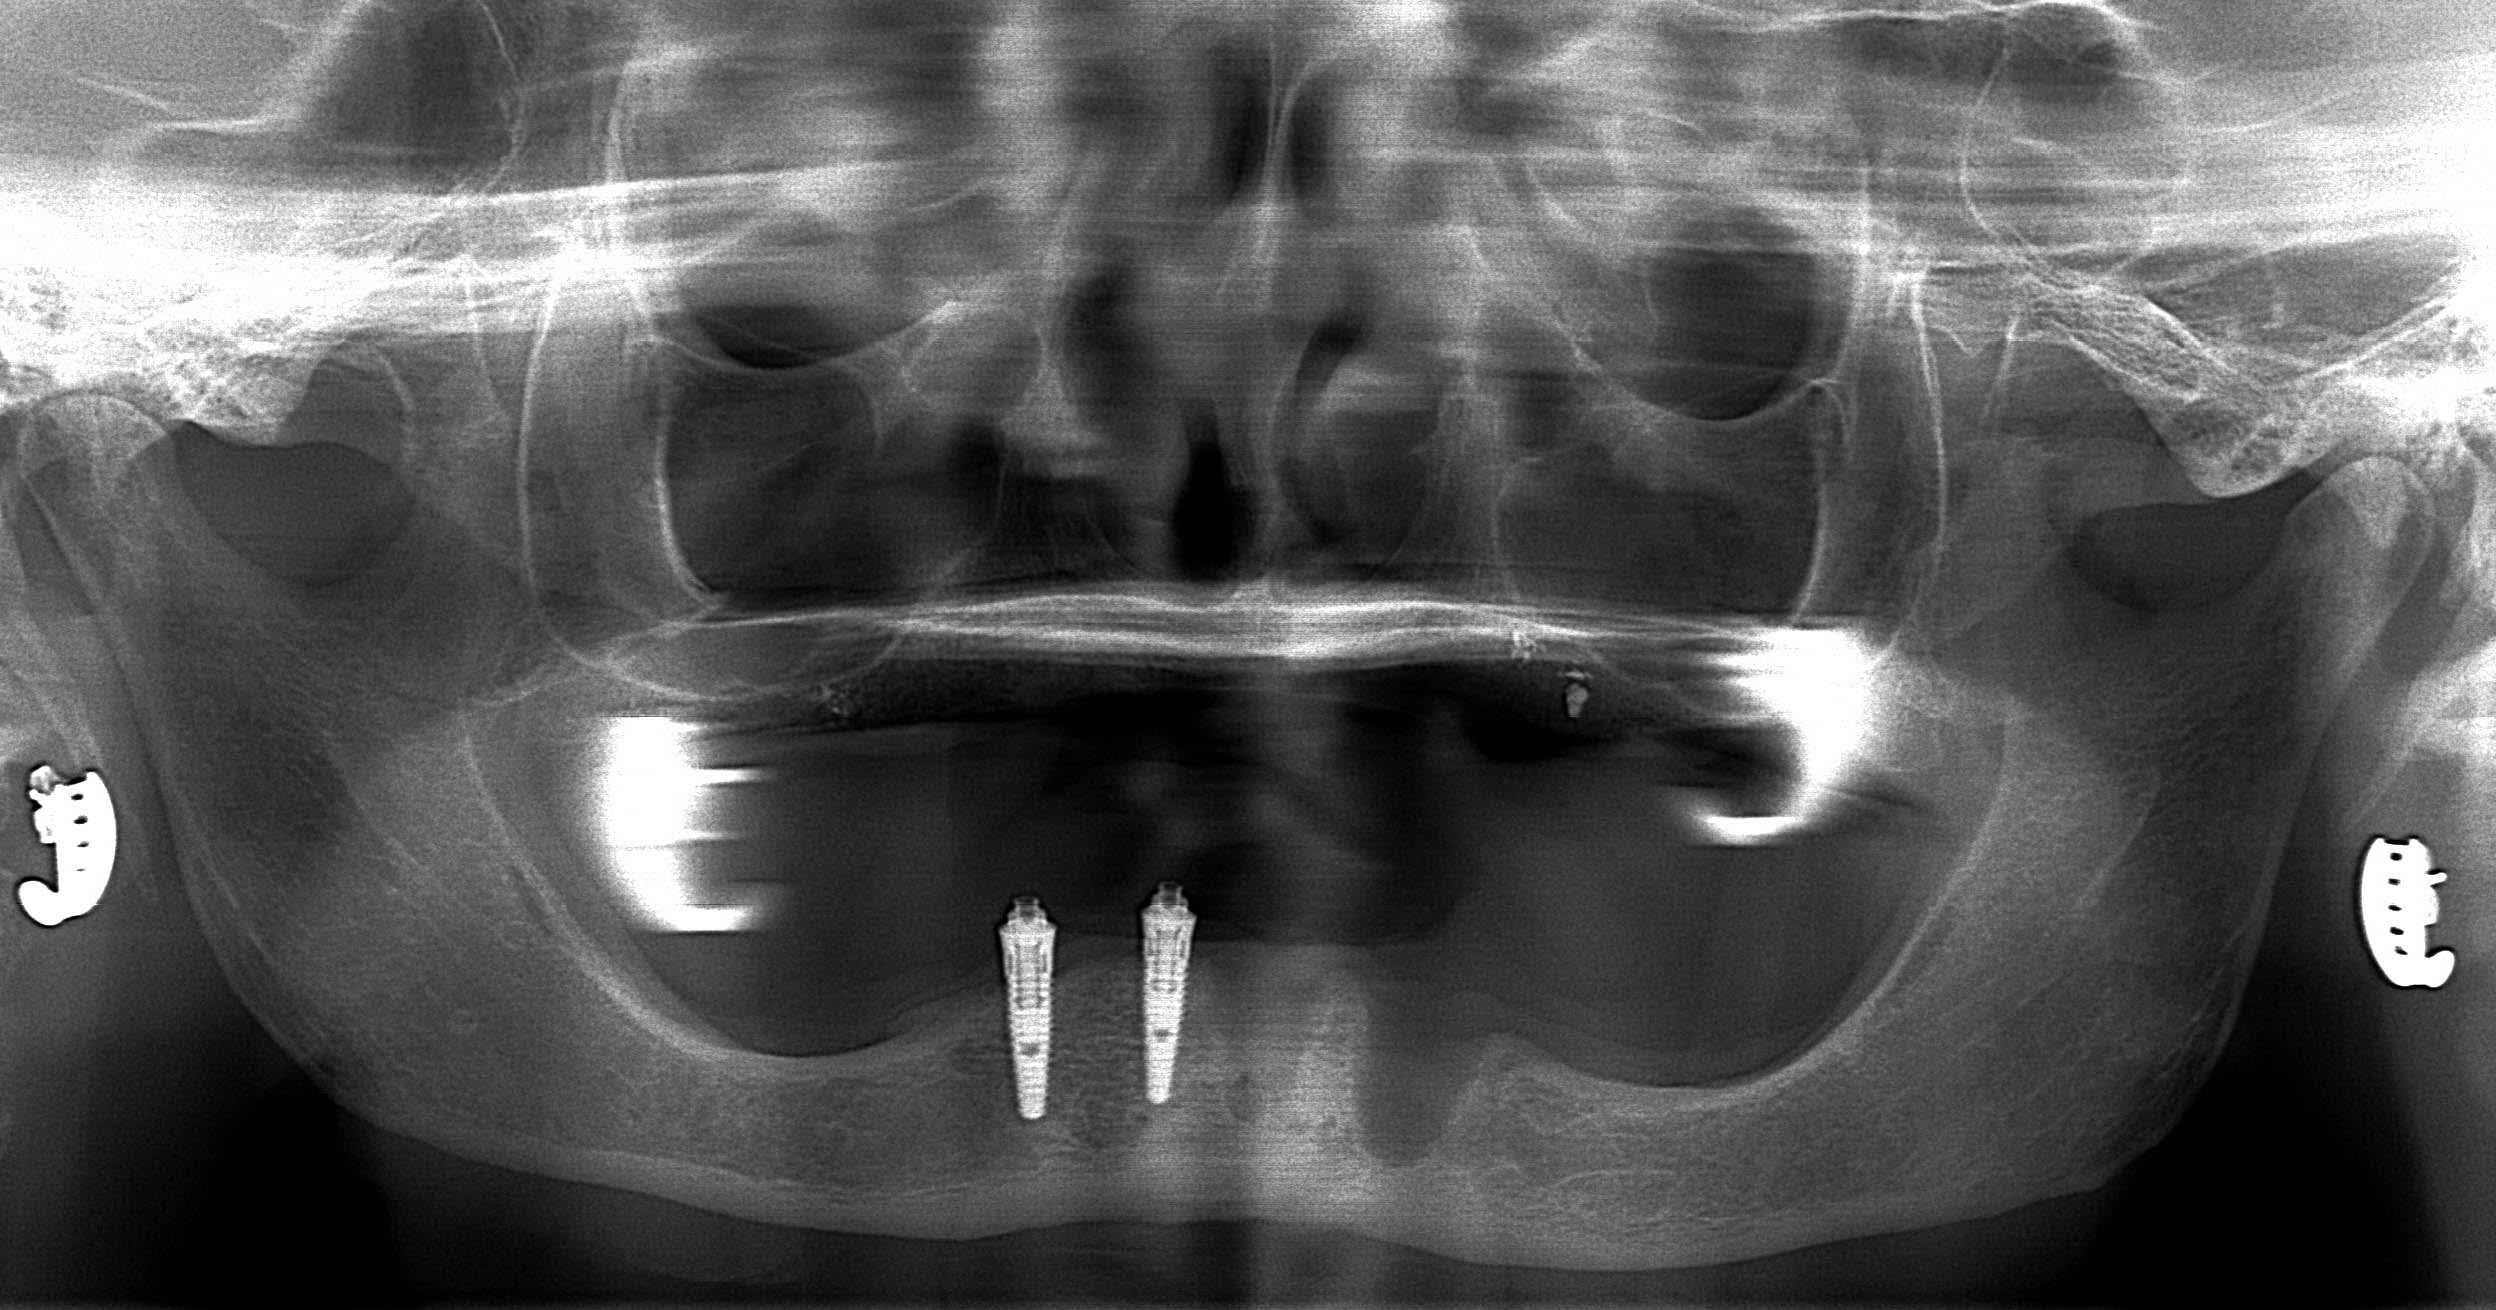

Tu veux dire que désormais, avec la perte de deux implants contigus avulsés pour cause de péri-implantite, le all on four est transformé en all on two?

PAC avec 2 locators , mal positionnés c'est vrai . Cela ne devrait pas lui couter un bras .

effectivement, c'est la chose la plus importante à gérer pour le moment.

je complète le cas;

82 ans

pose des implants par un praticien de Metz il y a10 ans. aucun problème particulier.

au final, les vis ont cassées dans les piliers multi-unit vendredi dernier.

intervention pour retirer le kyste et curetage avec reconstruction osseuse par ROG ( bioos, membrane et tutti quanti..)

petite précision, je mets des locators, c'est pas l'idéal, mais c'est mieux que rien.

plus tard , je pense ajouter 3 implants.